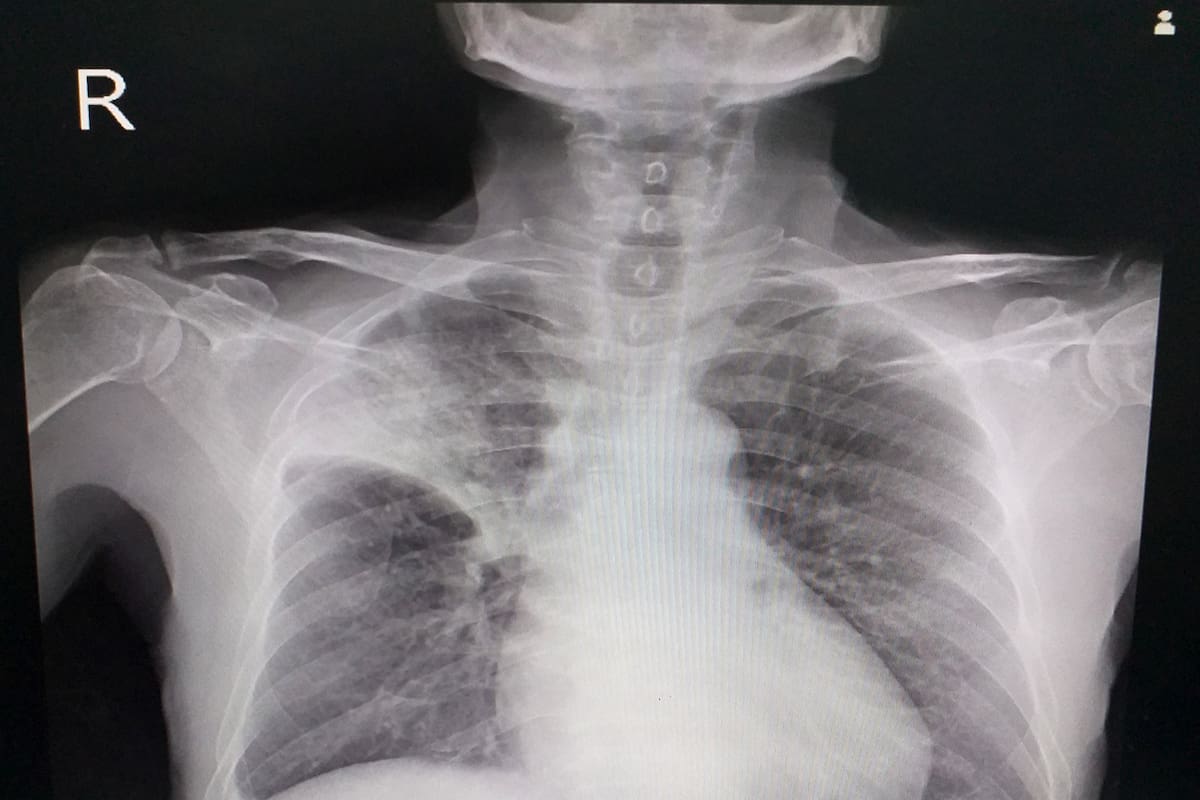

La justicia pampeana admitió parcialmente la demanda de un paciente contra dos médicos y sus compañías aseguradoras por mala praxis, cuando dos años después de ser operado de una válvula del corazón se sometió a una nueva intervención quirúrgica ante la sospecha de un tumor y encontraron una compresa de gasa de 30 centímetros, olvidada en el cuerpo en la primera cirugía.

El demandante había sido operado de una válvula del corazón y dos años después fue intervenido nuevamente, en otro centro médico, ante la sospecha de que podía tener un tumor o un quiste hidatídico y allí le encontraron el "oblito (cuerpo extraño) olvidado".

Concretamente, las fuentes precisaron que lo hallado se trataba de una compresa de gasa de 30 centímetros, que pudo ser encontrada en la segunda intervención.